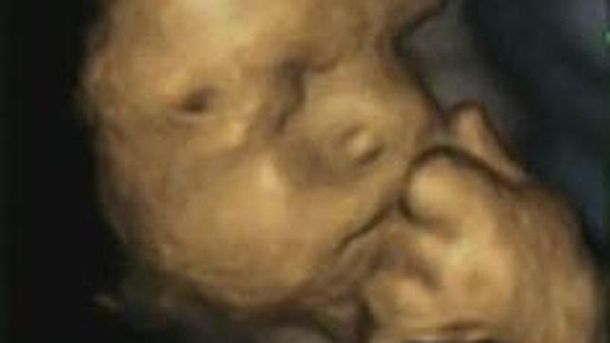

Los bebés se estresan antes de nacer y la fotografía de un feto dentro de la panza de su madre, nerviosa, lo comprobó. La manera de expresarlo moviendo su mano izquierda hacia su rostro es una demostración, según informa un nuevo estudio.

Para realizar el estudio, según indica ABC, se utilizaron ecografías 4D a través de las cuales observaron el comportamiento de 15 bebés.

Así, los investigadores demostraron que, mientras más estrés había sufrido la madre, con más frecuencia los fetos se tocaban la cara.